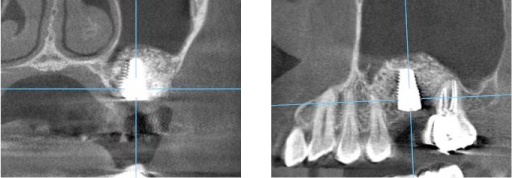

上顎洞までの距離はわずか2mmしかありません。 これではインプラントは出来ません。

下図のように上顎洞に骨になる材用を封入しました。

6か月経過後、再生した骨にインプラントを埋入しました。